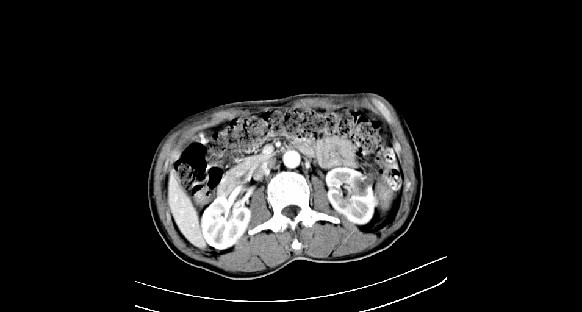

男性,70岁,体检b超发现左肾占位,请各位战友发表一下观点

左肾有两个病灶,且较大的病灶内可见点状钙化灶,增强扫描边缘也是呈渐进性强化,中央部分未见明显强化